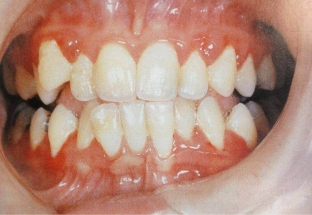

Hypertrophic gingivitis is characterized by burning sensation, bleeding gums and pain during brushing. Read about the appearance of the gums with gingivitis at estet-portal.com. The gum has a bright – red color, hypertrophy of the interdental spaces is determined. On examination, the gingival papillae are enlarged, edematous, hyperemia with a bluish tinge is determined. Gingival papillae have a glossy sheen. Gingival pockets often form and contain detritus. The dentogingival connection in hypertrophic gingivitis is not broken.

Fibrous gingivitis is manifested by the patient's complaints of gum enlargement, their pronounced density and spoiled aesthetic appearance. Such a gum can create discomfort when chewing food. At the same time, she has a pale – pink color and uneven surface. Examination reveals subgingival deposits.